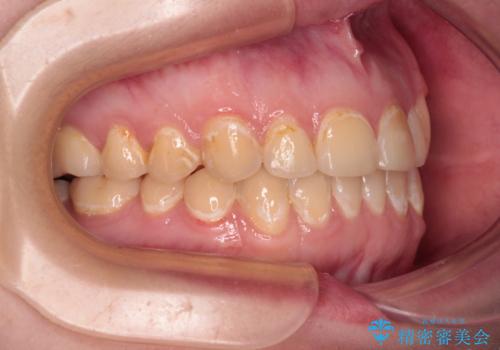

- 前歯のデコボコとクロスバイトが気になり、インビザラインによる矯正治療を希望して来院された患者様です。

上顎側切歯(上の真ん中から2番目の歯)が舌側転位している場合、無理して動かそうとすると歯髄壊死を起こすリスクが高い印象があります。

インビザライン単体でも治療は可能ですが、安全策としてインビザラインで歯列を移動する前に上顎前歯をワイヤー矯正で整え、その後上下歯列をインビザラインにて矯正治療を行うこととしました。

舌側転位している側切歯特有の、切縁の位置が不揃いであったり、根元が内側に引っ込んだ状態であったりという、インビザライン独特の仕上がりになることなく、きれいに整った歯列とすることができました。